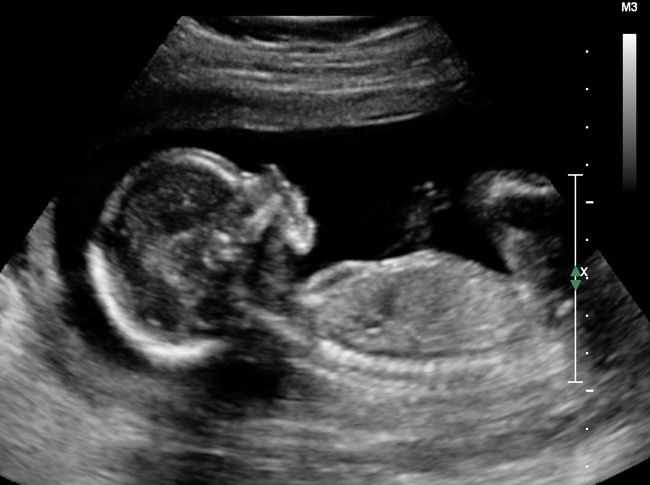

아내는 임신 7개월로 만삭의 상태였으며 뱃속의 아이는 산모의 장기손상과 과다출혈로 인해 그대로 사산되고 말았다.

더더욱 이 아이의 성별이 남성이 그토록 원했던 ‘남자아이’임이 밝혀졌다.